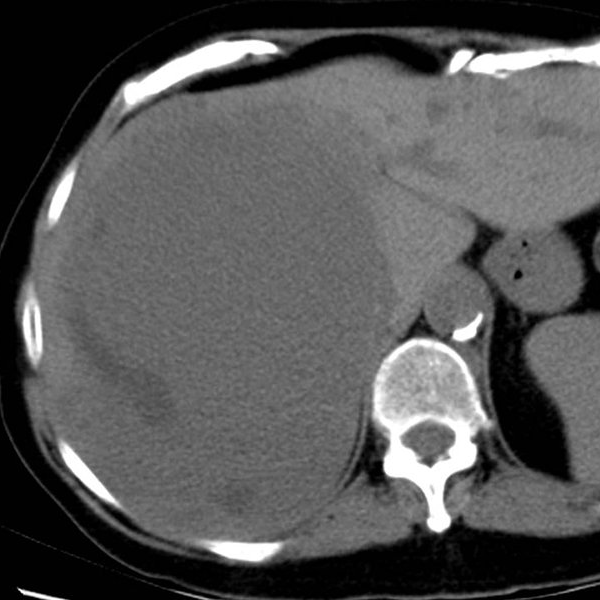

Hemangioma: es el tumor hepático más frecuente y es benigno. Generalmente se detectan de forma accidental cuando el paciente se somete a una ecografía o TC por otro motivo. Suelen ser asintomáticos y no requieren tratamiento quirúrgico.